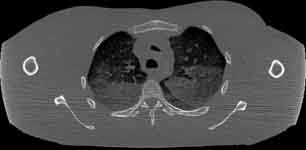

Visible Human male: Sectio transversalis 1361

CT

NMR

Pd T1 T2